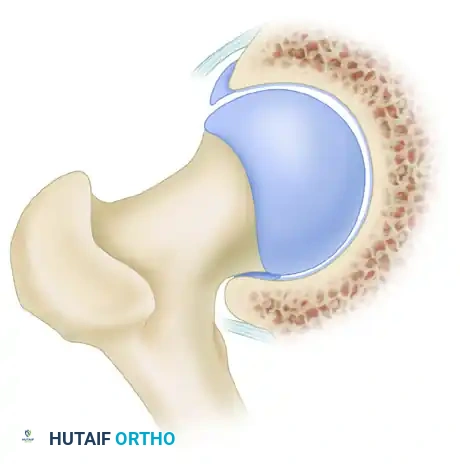

Pincer impingement is most commonly identified in middle-aged women and is characterized by focal or global overcoverage of the femoral head by the acetabulum.

In pincer impingement, the abnormal contact occurs directly between the prominent acetabular rim and the structurally normal femoral head-neck junction. This linear contact crushes the labrum between the bone of the femoral neck and the acetabular rim, causing intrasubstance tears and ossification of the labrum.

Clinical Pearl: The Contrecoup Lesion

As pincer impingement progresses and the anterior femoral neck repeatedly strikes the anterior acetabular rim, the femoral head is levered out of the socket posteriorly. This subluxation force drives the posteromedial femoral head into the posteroinferior acetabulum, creating a secondary "contrecoup" chondral injury in the posterior joint space.